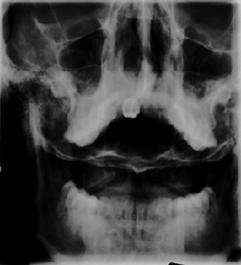

TRAUMA CERVICALA

antero-posterioara

Incidenta occipitomentala (odontoida)